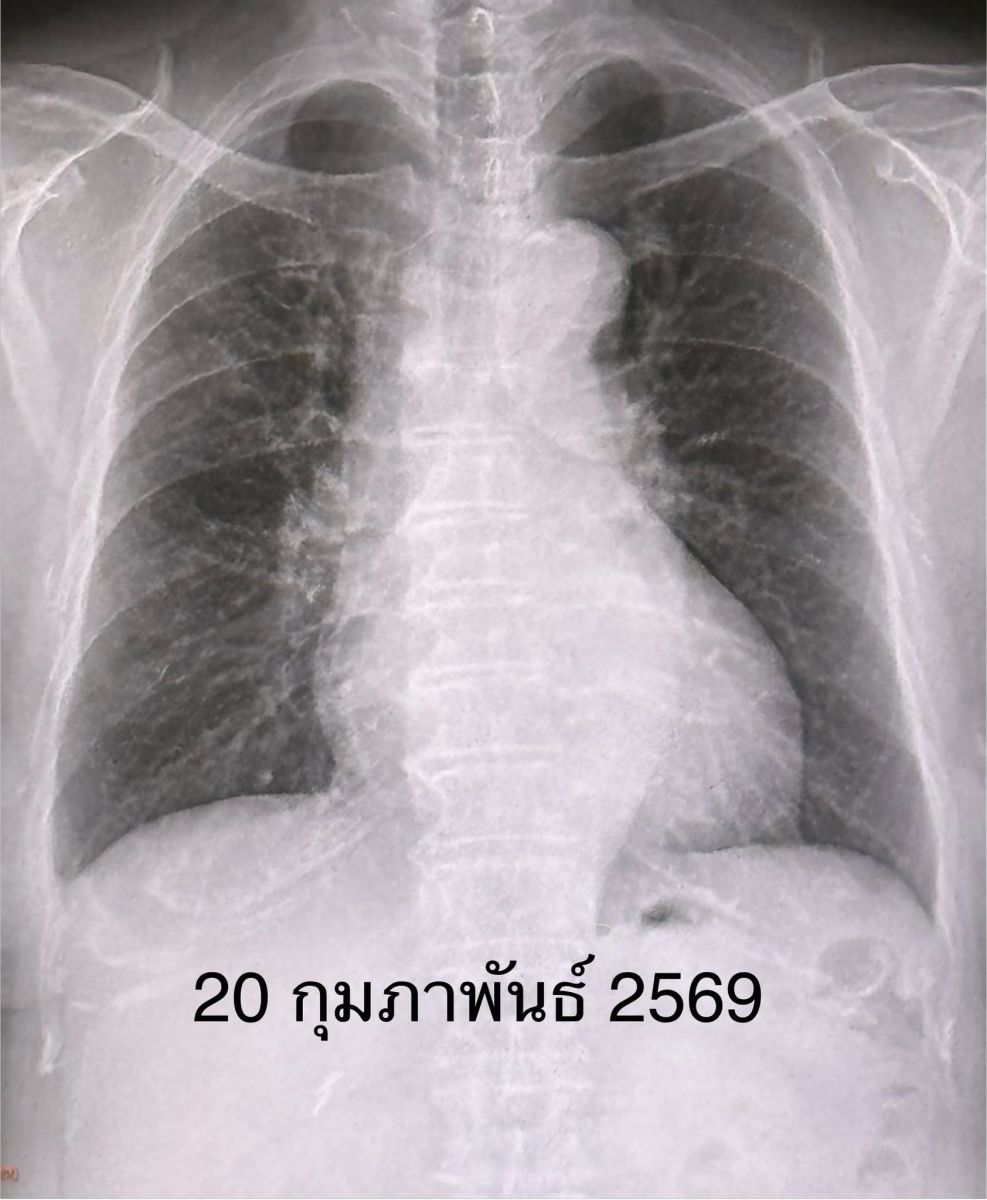

เคสนี้แพทย์วินิจฉัย ว่า โบคาไวรัส (Bocavirus) ทำให้เกิดปอดอักเสบ และภาวะหัวใจห้องบนเต้นระรัว (Arial fibrillation) ในผู้สูงอายุรายนี้ ซึ่งมีโรคประจำตัวเบาหวาน และไขมันสูง หลังให้ยา cordarone หัวใจกลับมาเต้นเป็นปกติ ให้การรักษาตามอาการ ไอลดลง ไม่มีเสมหะ ไม่มีไข้ ติดตามเอกซเรย์ปอดกลับมาปกติในเวลา 6 วัน